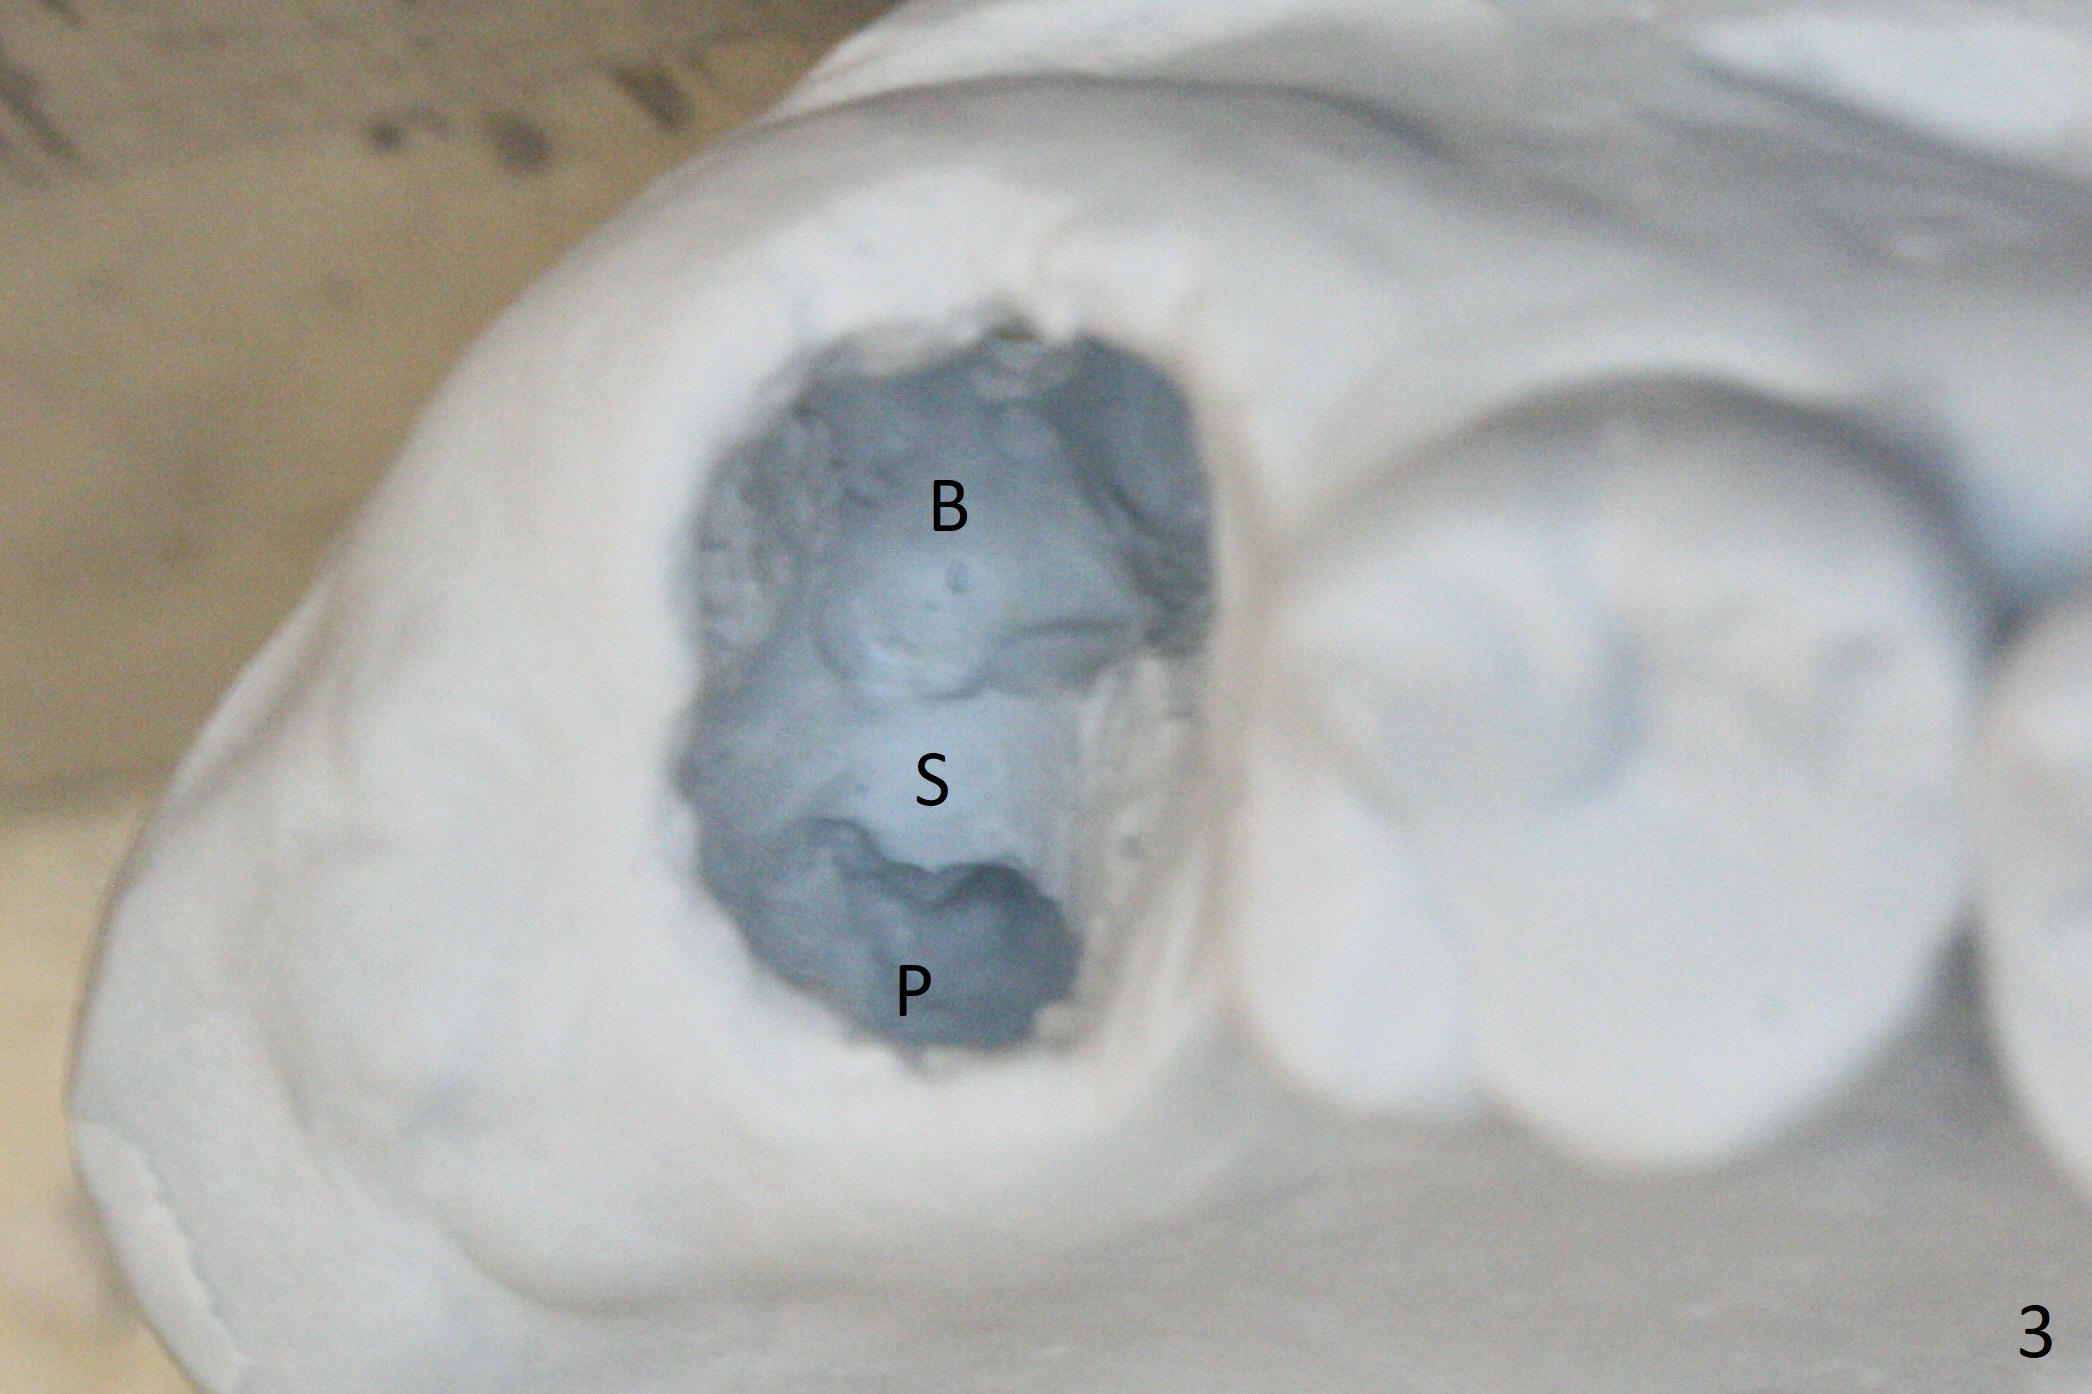

There is a fistula distal to the tooth #2 with deep pocket distopalatally (Fig.1 *), corresponding to palatal root fracture (Fig.2). There is a septum (Fig.3 S) between the buccal (B) and palatal (P) sockets. Osteotomy is initiated in the center of the septum (Fig.4 black circle). In fact the center of the socket is buccal (red circle), in which osteotomy should have been established because of the presence of the distopalatal bony defect associated with the root fracture and the distal fistula. The less ideal initial osteotomy leads to palatal placement of the implant and abutment (Fig.11 vs. 12).

Fig.5 shows the mesial slope of the socket (M), which is more or less the center of the socket mesiodistally. If the osteotomy were set up in the red circle (Fig.6) in the mesial slope (Fig.8 green dashed line), the trajectory of 4.5x11 mm dummy implant (Fig.7) would be more ideal (Fig.8 red outline) with more native bone contact. Finally a longer IBS implant is placed (4.5x15 mm, Fig.9,10) to achieve primary stability (50 Ncm). When the provisional is removed for impression 3 months 10 days postop, the implant is found to have been placed distopalatally (Fig.13), which should have been avoided. It appears essential to use guide for a distal implant. It is agonizing to re-encounter the off-axial implant (Fig.14) and the distopalatal access hole (Fig.15) 1 year post cementation. It is also amazing that the abutment screw has not loosened. A fair-sized piece of bone graft has just been removed buccally (Fig.15,16). The patient complains of sensitivity 2 years 3 months post cementation, although there is no abnormality around the implant crown. Guided surgery is essential to avoid restoration complication. There is no thread exposure nearly 3 years post cementation; in fact the apical portion of the abutment is covered by the bone (Fig.17,18).